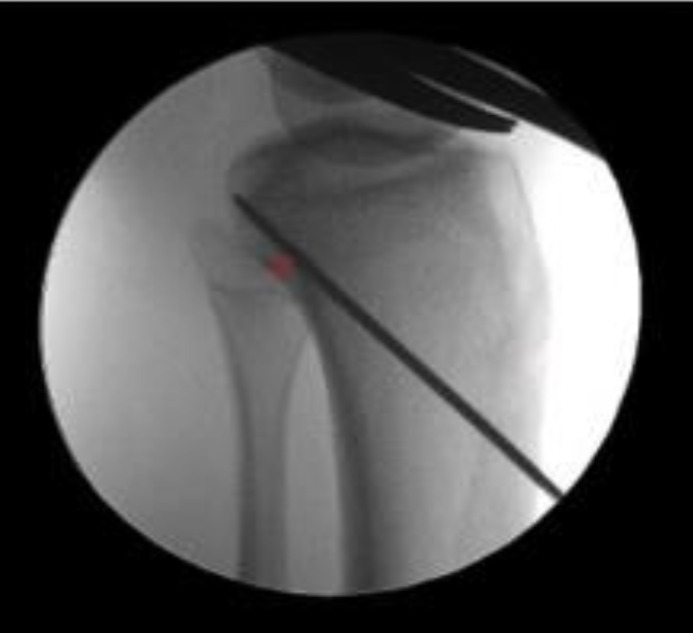

Figure 9.

Arthroscopic images of the medial femoral condylar roof and wall in a right knee. Top left – trochlear point. Top right – medial arch point. Bottom left – ALB tunnel reamed and passing suture, acorn reamer in location of PMB tunnel. Bottom right – 2 mm bone bridge between ALB tunnel and PMB tunnel location

After diagnostic arthroscopy through anterolateral and anteromedial portals, the first surgical step involves identification of the PCL femoral attachments of the ALB and PMB and outlining them with an arthroscopic coagulator. The ALB tunnel should be placed as distal as possible, adjacent to the edge of the articular cartilage (11). The PMB center is a mean of 8.6 mm distal to the articular cartilage, and the tunnel should be placed slightly posterior to the ALB (6, 11). The diameters of the ALB and PMB tunnels should be 11 mm and 7 mm, respectively, and each closed socket tunnel should be reamed to a depth of 25 mm. A notch is made on the posteroinferior aspect of the PMB tunnel to facilitate later screw fixation because the bone is quite dense at this location. A bone bridge of 2 mm between the femoral tunnels should be maintained (11) [Figure 9]. shows arthroscopic images which demonstrate these pertinent anatomic landmarks of the medial femoral condyle and the appropriate locations for reaming of the femoral tunnels.